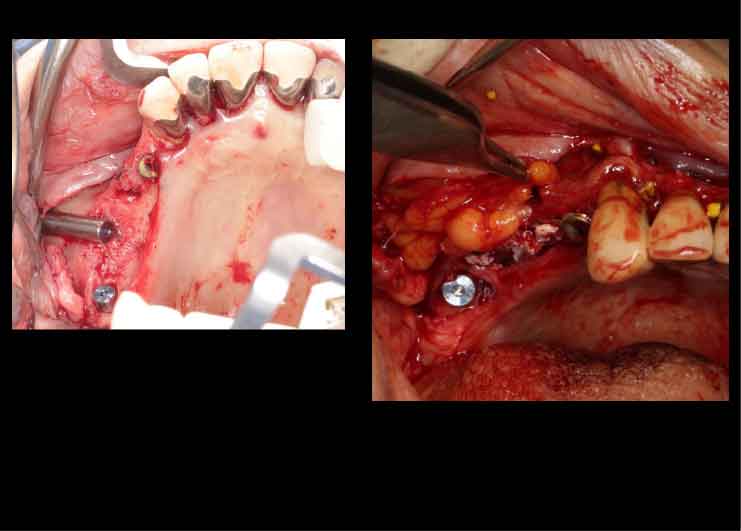

歯周病でインプラント、歯が脱離。

上あごの骨が非常に薄く、そのままではインプラントを埋め込むことができないため、Xマークを使用したザイゴマ(頬骨)インプラントおよびプテリゴイド(蝶形骨)インプラントを行ったケース。

脂肪組織をインプラント表面に挿入

血液循環を良くして、筋肉の可動域を広げます。